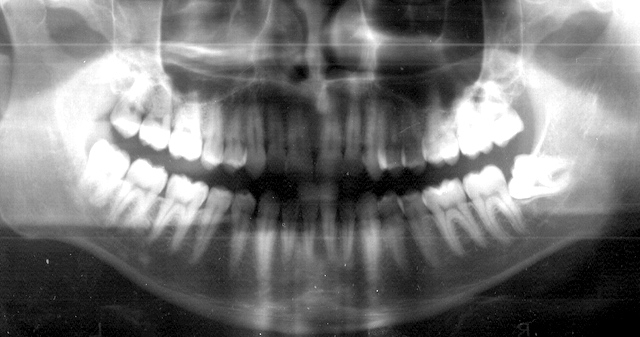

Radiografia Panoramica , com 7 dentes do Sisos!